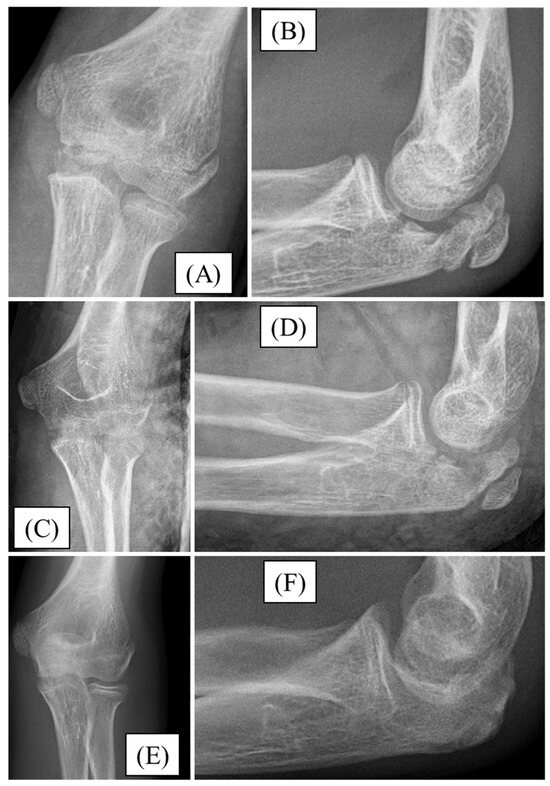

3.3. Case 3